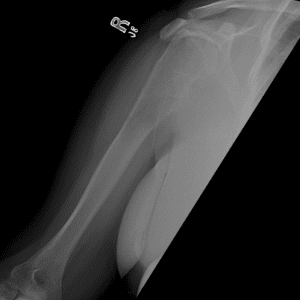

Pediatric Radiographs